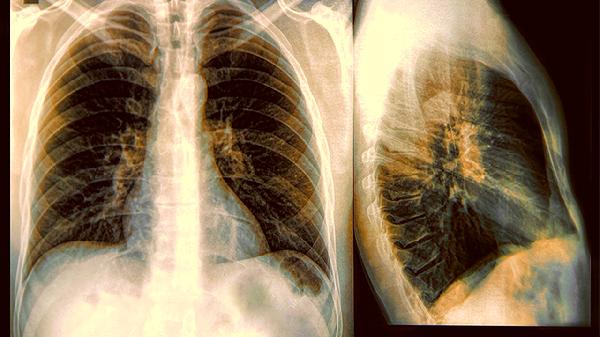

50岁女子确诊慢阻肺,喝“百合水”养肺,一年后肺部状况咋样

二、一年后的肺腑真相

案例中的女士坚持饮用后发现,晨起撕心裂肺的咳嗽从"每日闹钟"变成了"偶尔来访",但肺功能检查时的吹气球测试,数值依旧在及格线徘徊。这提醒我们,主观感受和客观指标常玩捉迷藏。